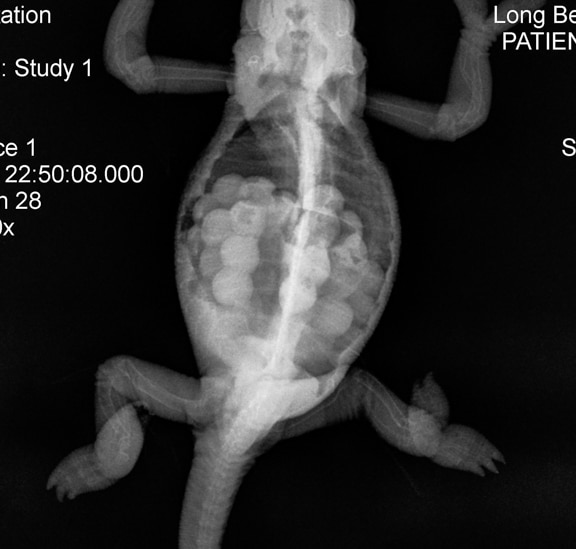

I took her to a vet who takes exotics, and got her checked and x-rayed. The doctor didn't seem too knowledgable on chameleons, and told me quickly that if she had already laid her eggs, she probably wasn't egg bound and likely didn't have any left inside her. She agreed that my girl was plump, though, and recommended we go ahead with the x-ray. I'll post them here for y'all to see as well, but she didn't see any eggs in there, and told me Reggie might have gas (?) inside her, but didn't elaborate much, just sent us on our way.

I wonder if any of you can see the egg in these x-rays, because I don't know if I can. There is one circular blob that doesn't look like an egg at all compared to other cham x-rays, but maybe that was it in the end, I'm not sure. I included a comparison x-ray I found on google that shows many eggs, so I know it's not the best to compare Reggie's to, but the little blob in her second view of her abdomen doesn't look like as opaque as the eggs in the comparison.